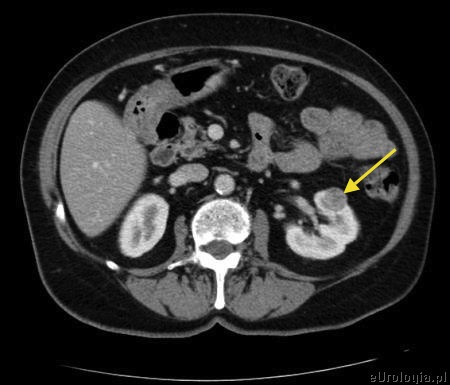

Mam 58 lat i 3 tygodnie temu w USG brzucha wykryto u mnie guz nerki średnicy około 2 cm. Obecność guza w nerce potwirdziło badanie KT jamy brzusznej. Urolog, który będzie mnie operował twierdzi, że guz jest mały i dobrze zlokalizowany więc spróbuje zrobić enukleację - oszczędzi mi nerkę. Czy enukleacja guza nerki jest zabiegiem bezpiecznym? Czy nie lepeiej usunąć od razu całą nerkę.

W przypadku małych guzów nerki, zlokalizowanych brzeżnie optymalnym sposobem leczenia są operacje polegające na usunięciu guza z oszczędzeniem nerki. Wiele badań dowiodło, ze